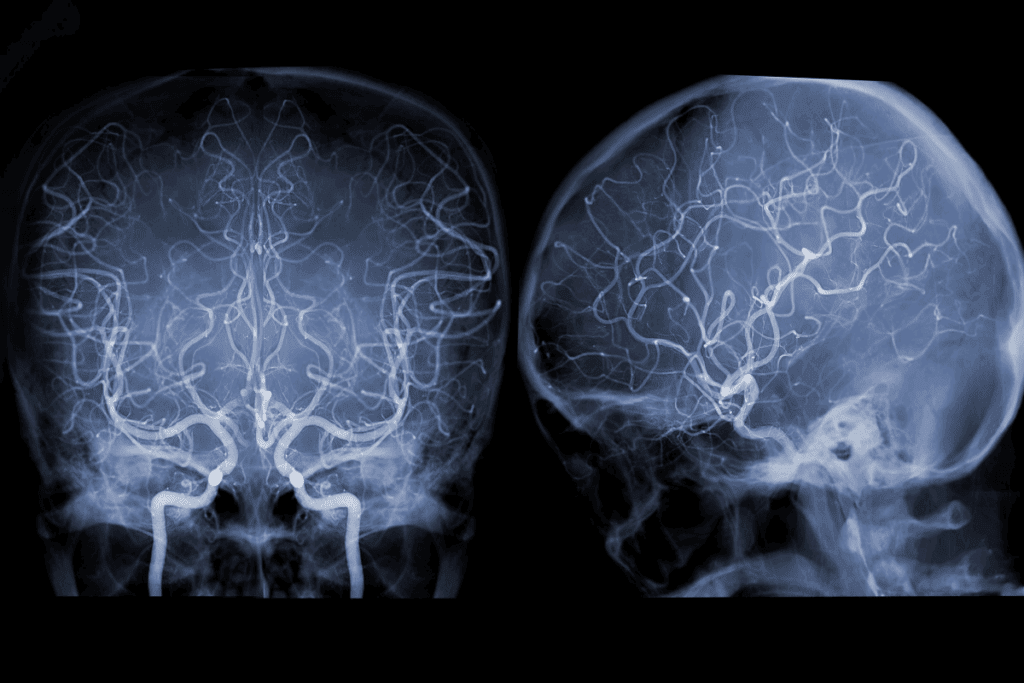

Imaging Equipment and Angiography Suite Setup

High-quality imaging is vital for treating cerebral aneurysms. We use advanced angiography suites with high-resolution digital subtraction angiography (DSA). These systems give us real-time images, helping us navigate the brain’s blood vessels accurately.

The angiography suite is set up for the best imaging and safety. It includes a biplane angiography system. This gives us two views of the blood vessels at once, helping us treat the aneurysm better.